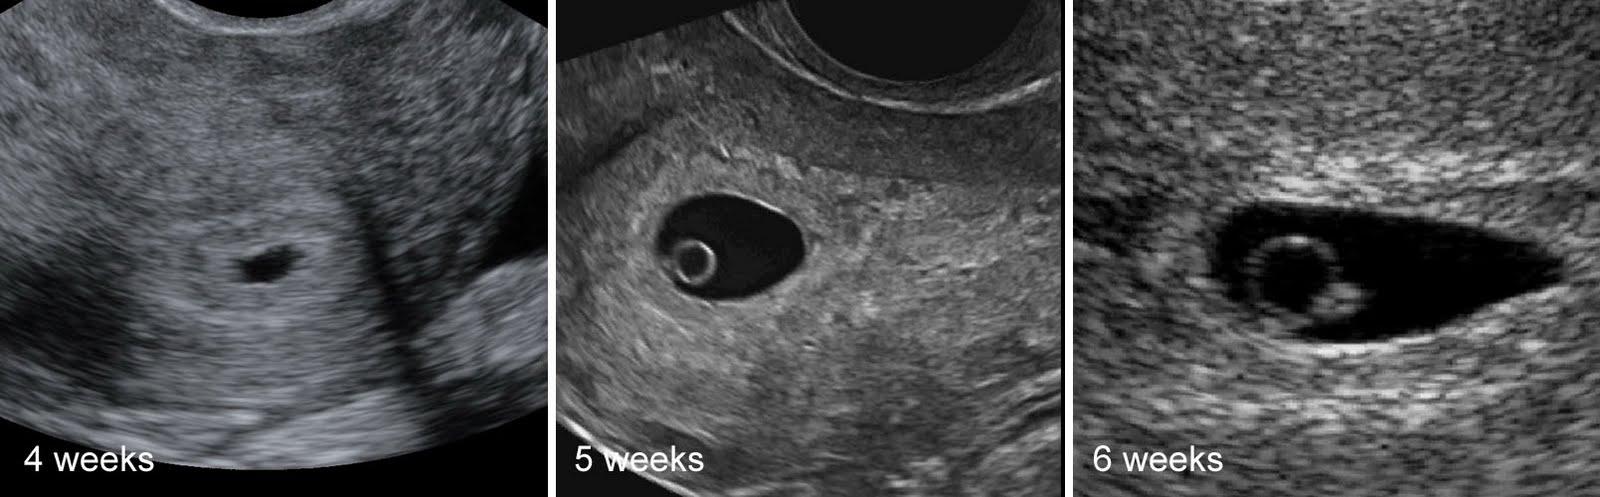

@kockakacka teda, 3mm to tak končíš 6tt ne?? 🙂 ale krása, není nad to, to mít potvrzený od DR 🙂

@kockakacka čauky. Tak já zrovna došla od Dr. 5+3 a primitivní srdíčko.